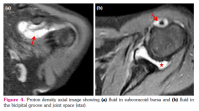

a) Synovial hypertrophy score: Thirteen (40.6%) joints in nine patients revealed synovial hypertrophy with a mean grade score of 0.7±0.9 (Figure 1 a, b). Five joints had Grade I and eight joints had Grade II synovial hypertrophy (Figure 2a). The number of joints with synovial hypertrophy in sJIA, ERA, and undifferentiated JIA were seven (53.8%), four (30.7%), and two (15.3%) joints, respectively.

b) BME score: Twenty-one (65.6%) joints in 13 patients revealed BME with a mean grade score of 1.1±1.0 (Figure 1c, d). The number of joints which had Grade I, II and III BME scores were 11, seven, and three, respectively (Figure 2a). The number of joints with BME in sJIA, ERA, and undifferentiated JIA was 13 (61.9%), five (23.8%), and three (14.2%) joints, respectively. Of these 21 joints, only two joints revealed BME with no other findings and the rest 19 joints showed synovial effusion or one or the other MRI parameter of joint inflammation. There was no statistically significant difference in the occurrence of BME in sJIA subset versus the rest of the JIA subsets (p=0.823).

In addition, the presence or absence of synovial effusion on MRI was also noted. Joint effusion was seen as hyperintensity adjacent to synovium on post-contrast T1-weighted images.